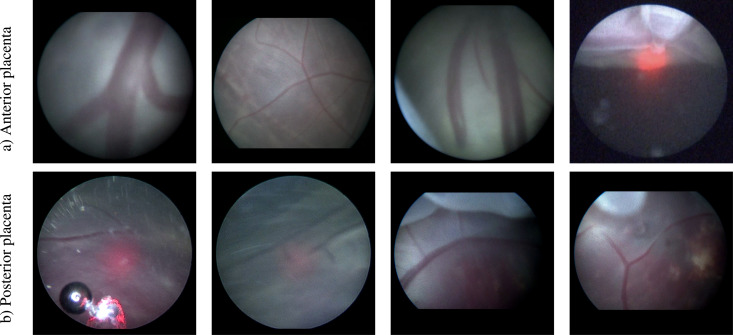

图13. 两种胎盘类型(a)前壁和(b)后壁胎盘的视频帧示例。我们展示了前壁胎盘病例在视野内表现出比后壁胎盘病例更好的胎盘血管可见性,这影响了两种类型的分割性能。